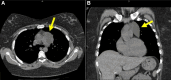

Case summary: We present the atypical presentation of a progressive, left-sided pericardial cyst. The patient underwent surgical resection with recurrence within 5 months.